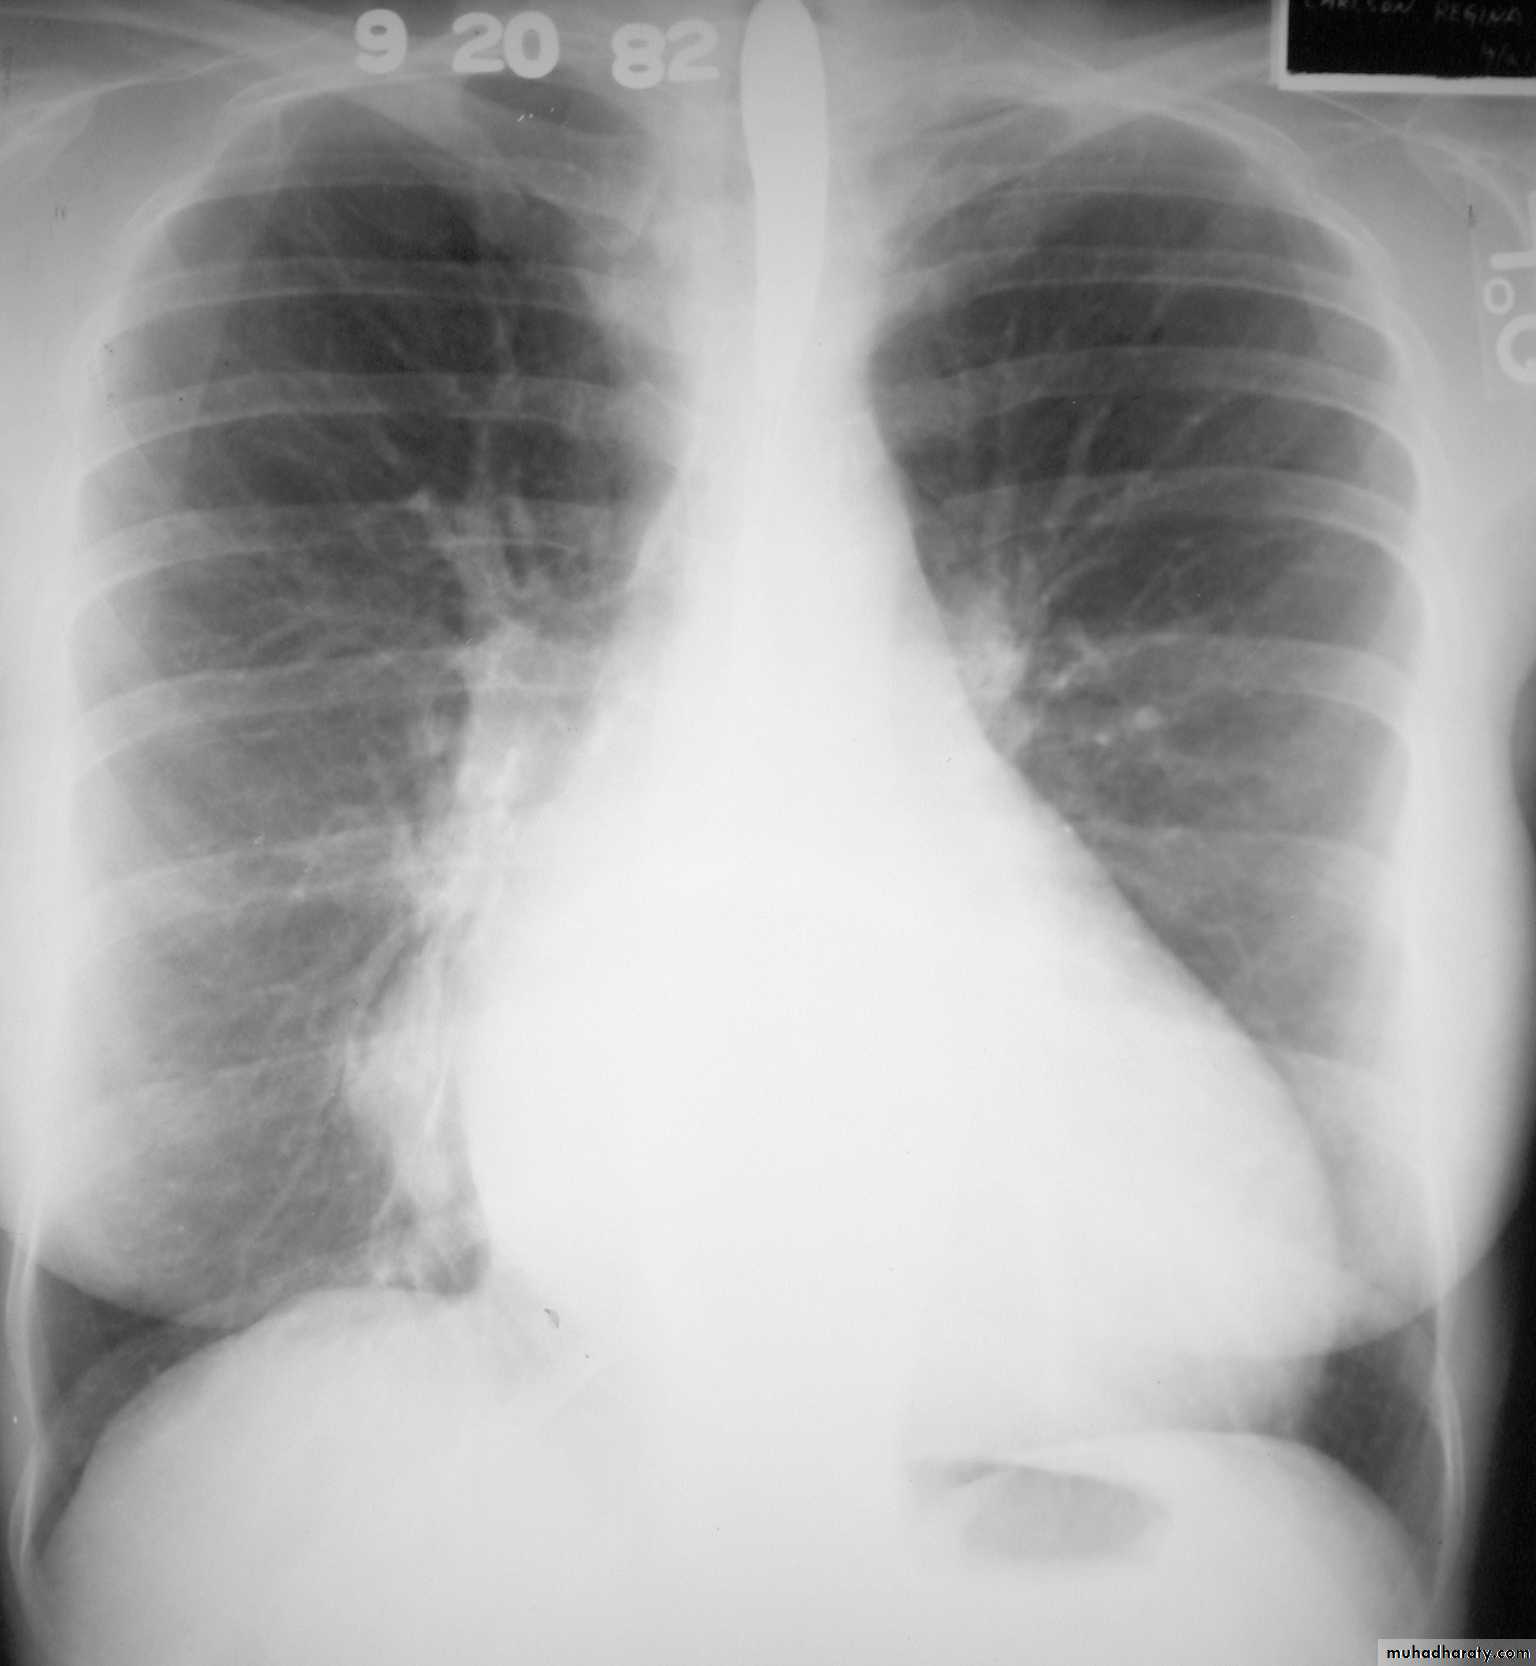

Pericardial effusion

occur when fluid collects in the pericardial space (a normal pericardial sac contains approximately 30-50 ml of fluid).radiographic features

Plain radiograph

a very small pericardial effusion can be occult on plain film, greater than 200 ml required to be visible radiographicly.

there can be globular enlargement of the cardiac shadow giving a water bottle configuration; known as Globe shape heart or pumpkin shape heart .